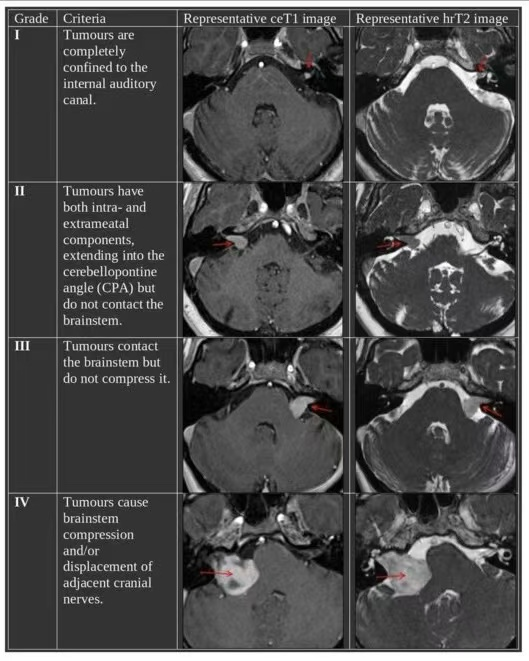

Koos分级

Koos分级系统将听神经瘤分为1至4级,其中4级表示肿瘤体积较大,通常已达到脑干受压状态。

Koos 4级听神经瘤手术难度大、风险高,需要经验丰富的神经外科团队进行精细化操作,才能有效减少术中并发症和术后功能损伤。